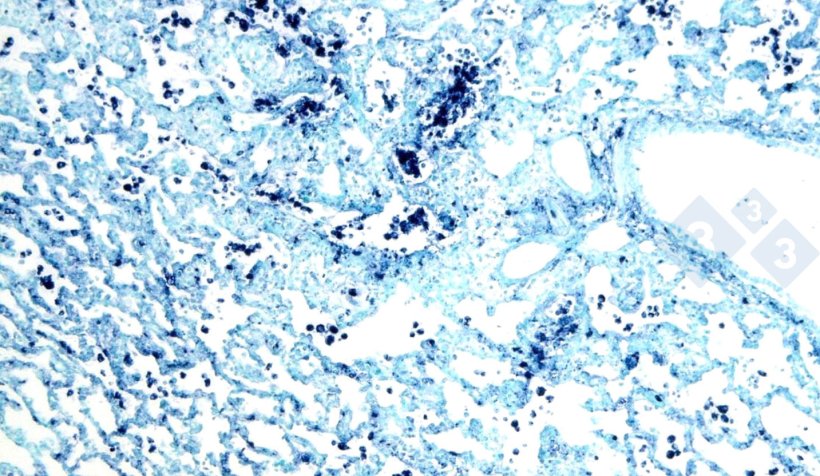

Figure 4 : Hybridation in situ pour le circovirus porcin 2 (PCV2) dans un poumon atteint de pneumonie interstitielle.